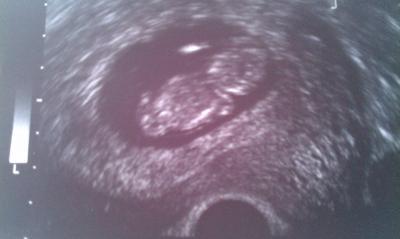

Muckel ist nun 46,2 mm groß :) und hat ein ordentliches Bäuchlein. Hat mit einem Arm geboxt, der kleine Rocker, und war ordentlich am Zappeln. Am 17.12 machen wir nochmal einen US, weil mein Mann noch Angst hat. Am 1. Weihnachtstag sagen wir es seinen Eltern. Sie bekommen dann einen Bilderrahmen mit sämtlichen US Bildern (abfotografiert). Aber aufhängen dürfen sie es dann noch nicht, weil es sonst noch keiner wissen soll.